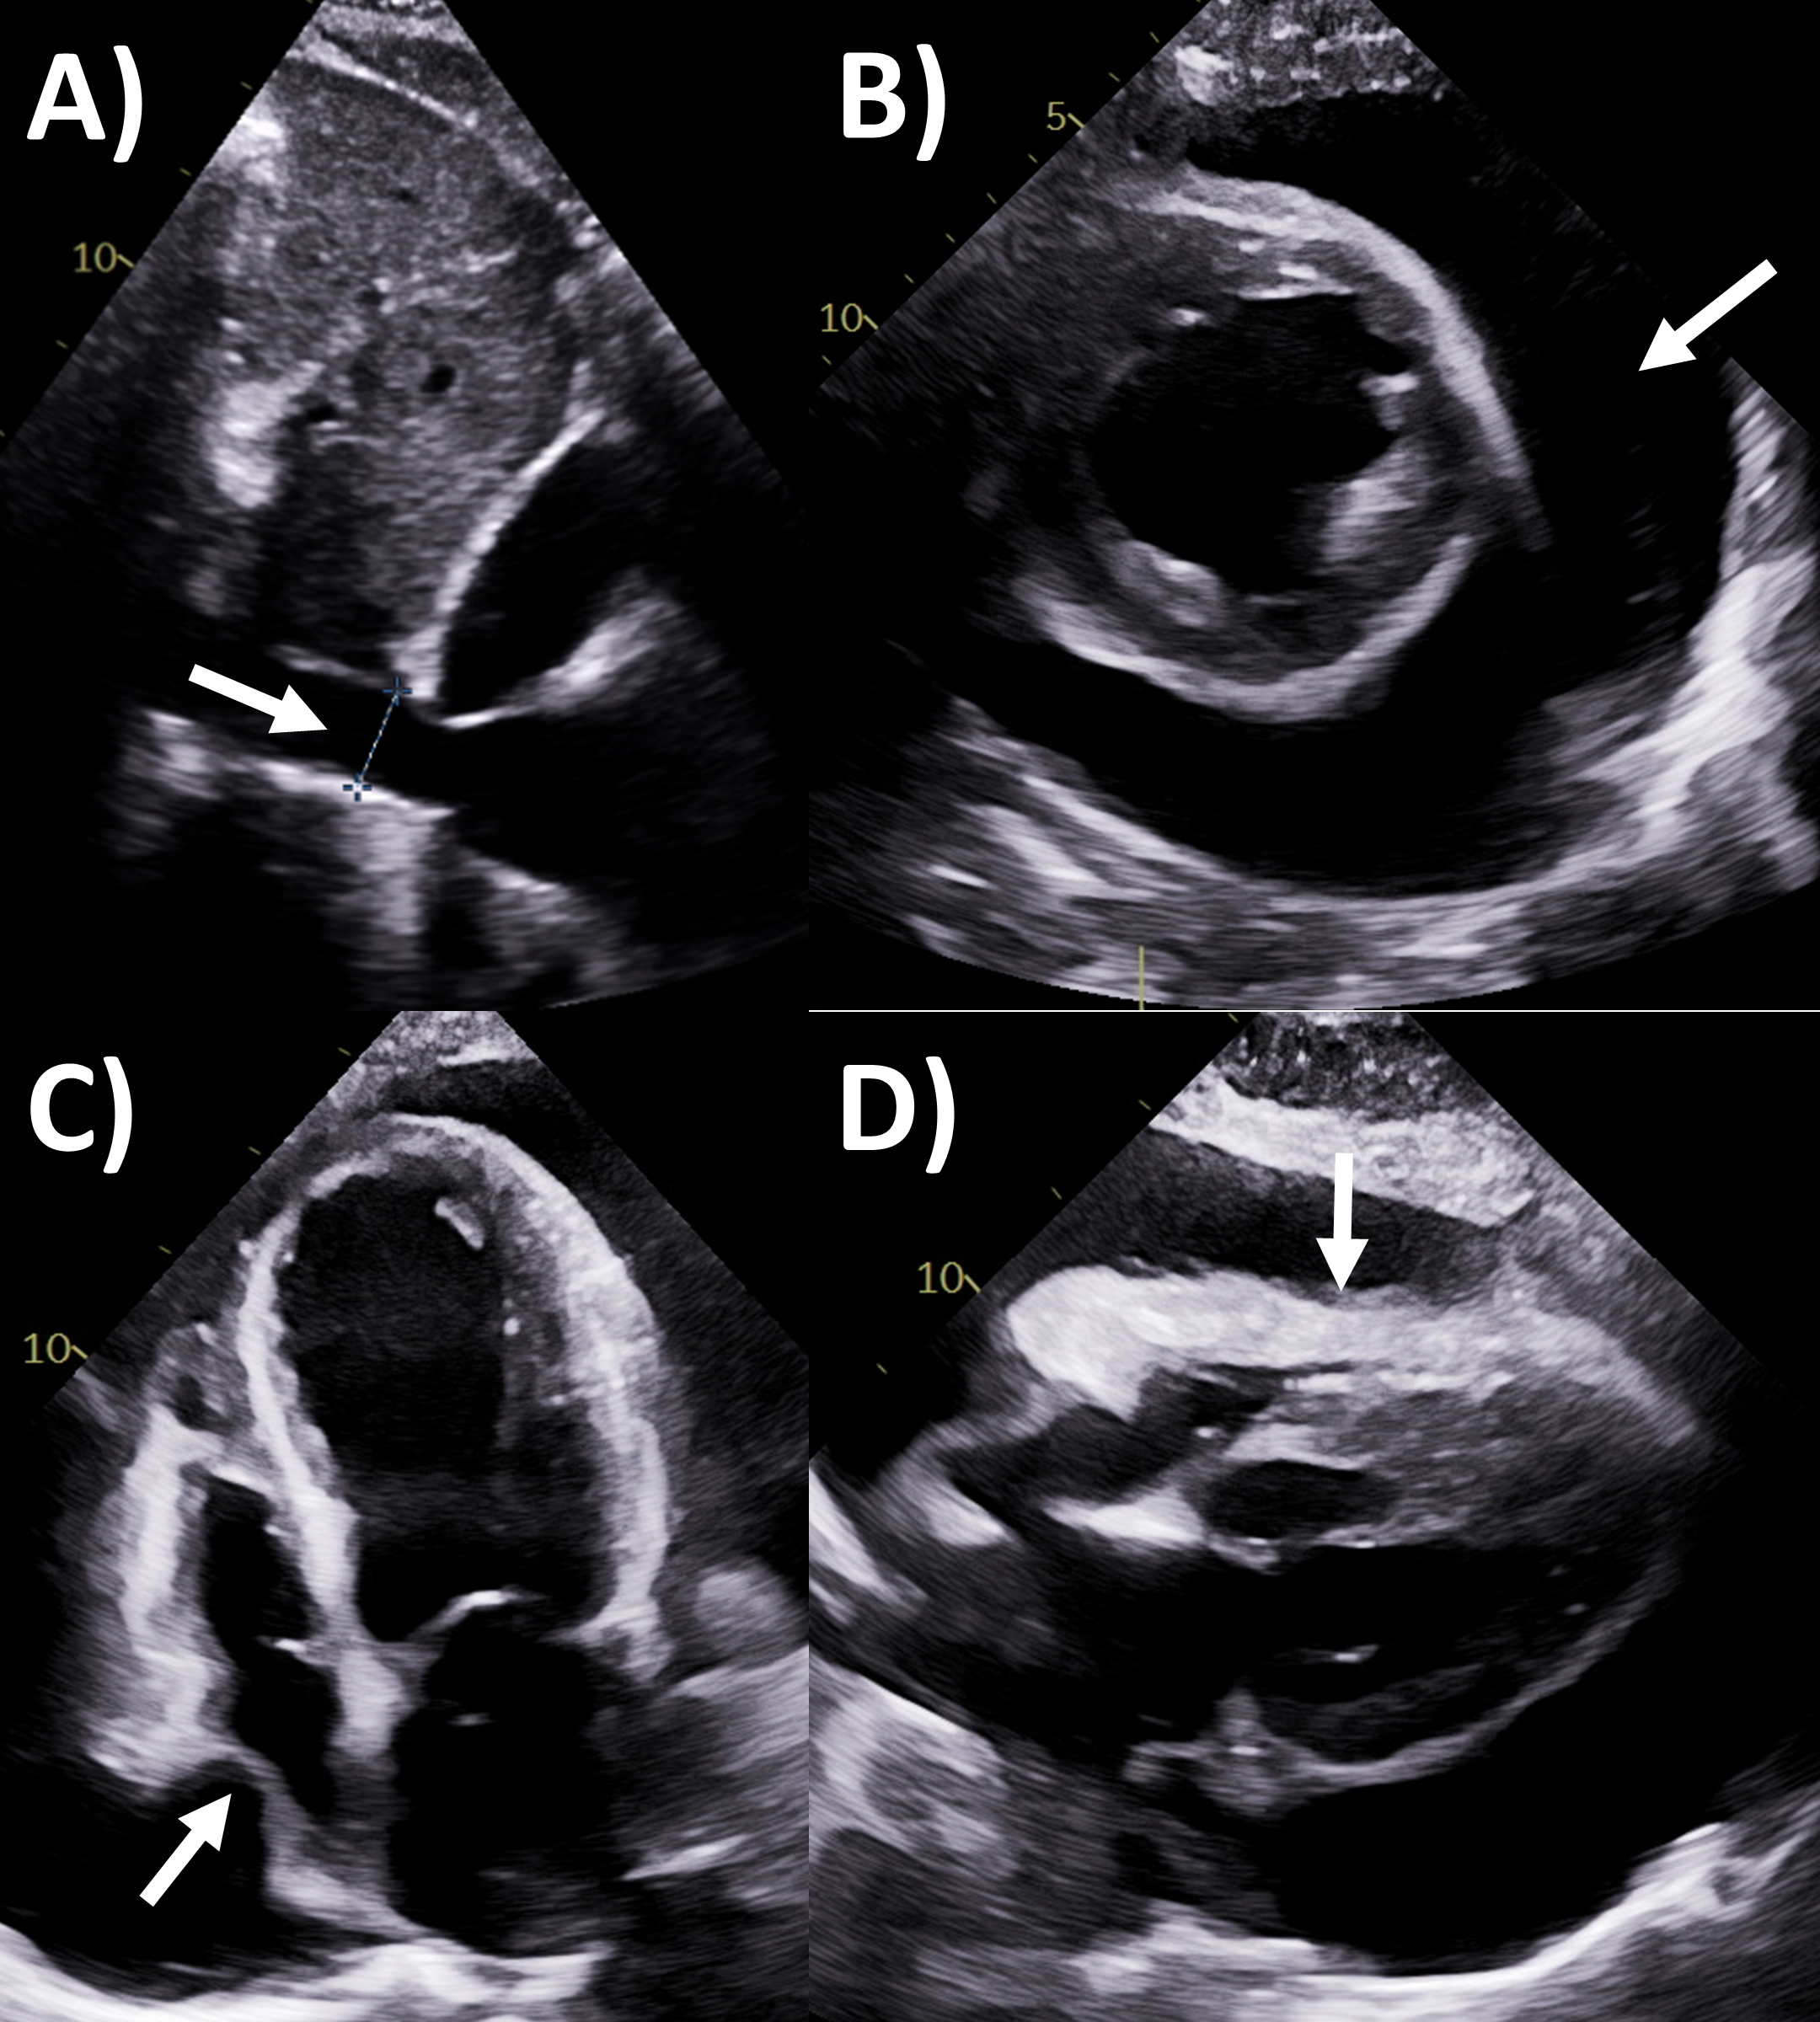

echocardiographic criteria according to guidelines (Fig. 2) include dilated

inferior vena cava with minimal (

Fig. 2.Echocardiography evaluation of pericardial tamponade. (A)

Dilated inferior vena cava (2.7 cm) with minimal

Pericardial constriction is a feared chronic complication of pericardial

same etiology but often challenging to diagnose [1, 35]. Echocardiography is also

the first-line and often self-sufficient modality for evaluation of constrictive

physiology [2, 36]. The Mayo Clinic Criteria being the recommended algorithm for

diagnosing this entity that is frequently challenging to distinguish from

restriction or diastolic dysfunction, with several key findings shown in (Fig. 3)

[36, 37, 38]. The first part of the algorithm has the dual criteria of mitral inflow

E/A ratio

Fig. 3.Multi-modality imaging evaluation of constrictive pericarditis.

Echocardiography (A) dilated inferior vena cava (2.3 cm) with minimal

Of note, in the Mayo Clinic Criteria derivation study, the presence of

respirophasic ventricular septal shift and either medial e’ velocity

MRI is actually a valuable second-line but under-utilized imaging tool for

evaluating constrictive pericarditis [2]. Standard cine imaging with steady state

free precession or gradient echo sequences not only assess chamber size and

function, but also typical constriction findings such as abnormal

interventricular septal motion, wall tethering, conical ventricular deformities,

and dilated inferior vena cava, while free breathing sequences allows assessment

for respirophasic septal shift (Fig. 3) [2, 50]. Pericardial thickness often

increased in constrictive pericarditis can be assessed by these bright-blood

sequences or black-blood spin echo sequences, as well as dilated inferior vena

cava. Quantitative measures include lower short-axis cardiac area at

end-inspiration/end-expiration, and higher relative atrial volume index ratio

(left versus right) to be present in constrictive pericarditis [51, 52].

Acquiring phase-contrast sequences real-time over 10 seconds with free breathing

an detect mitral and tricuspid inflow, with